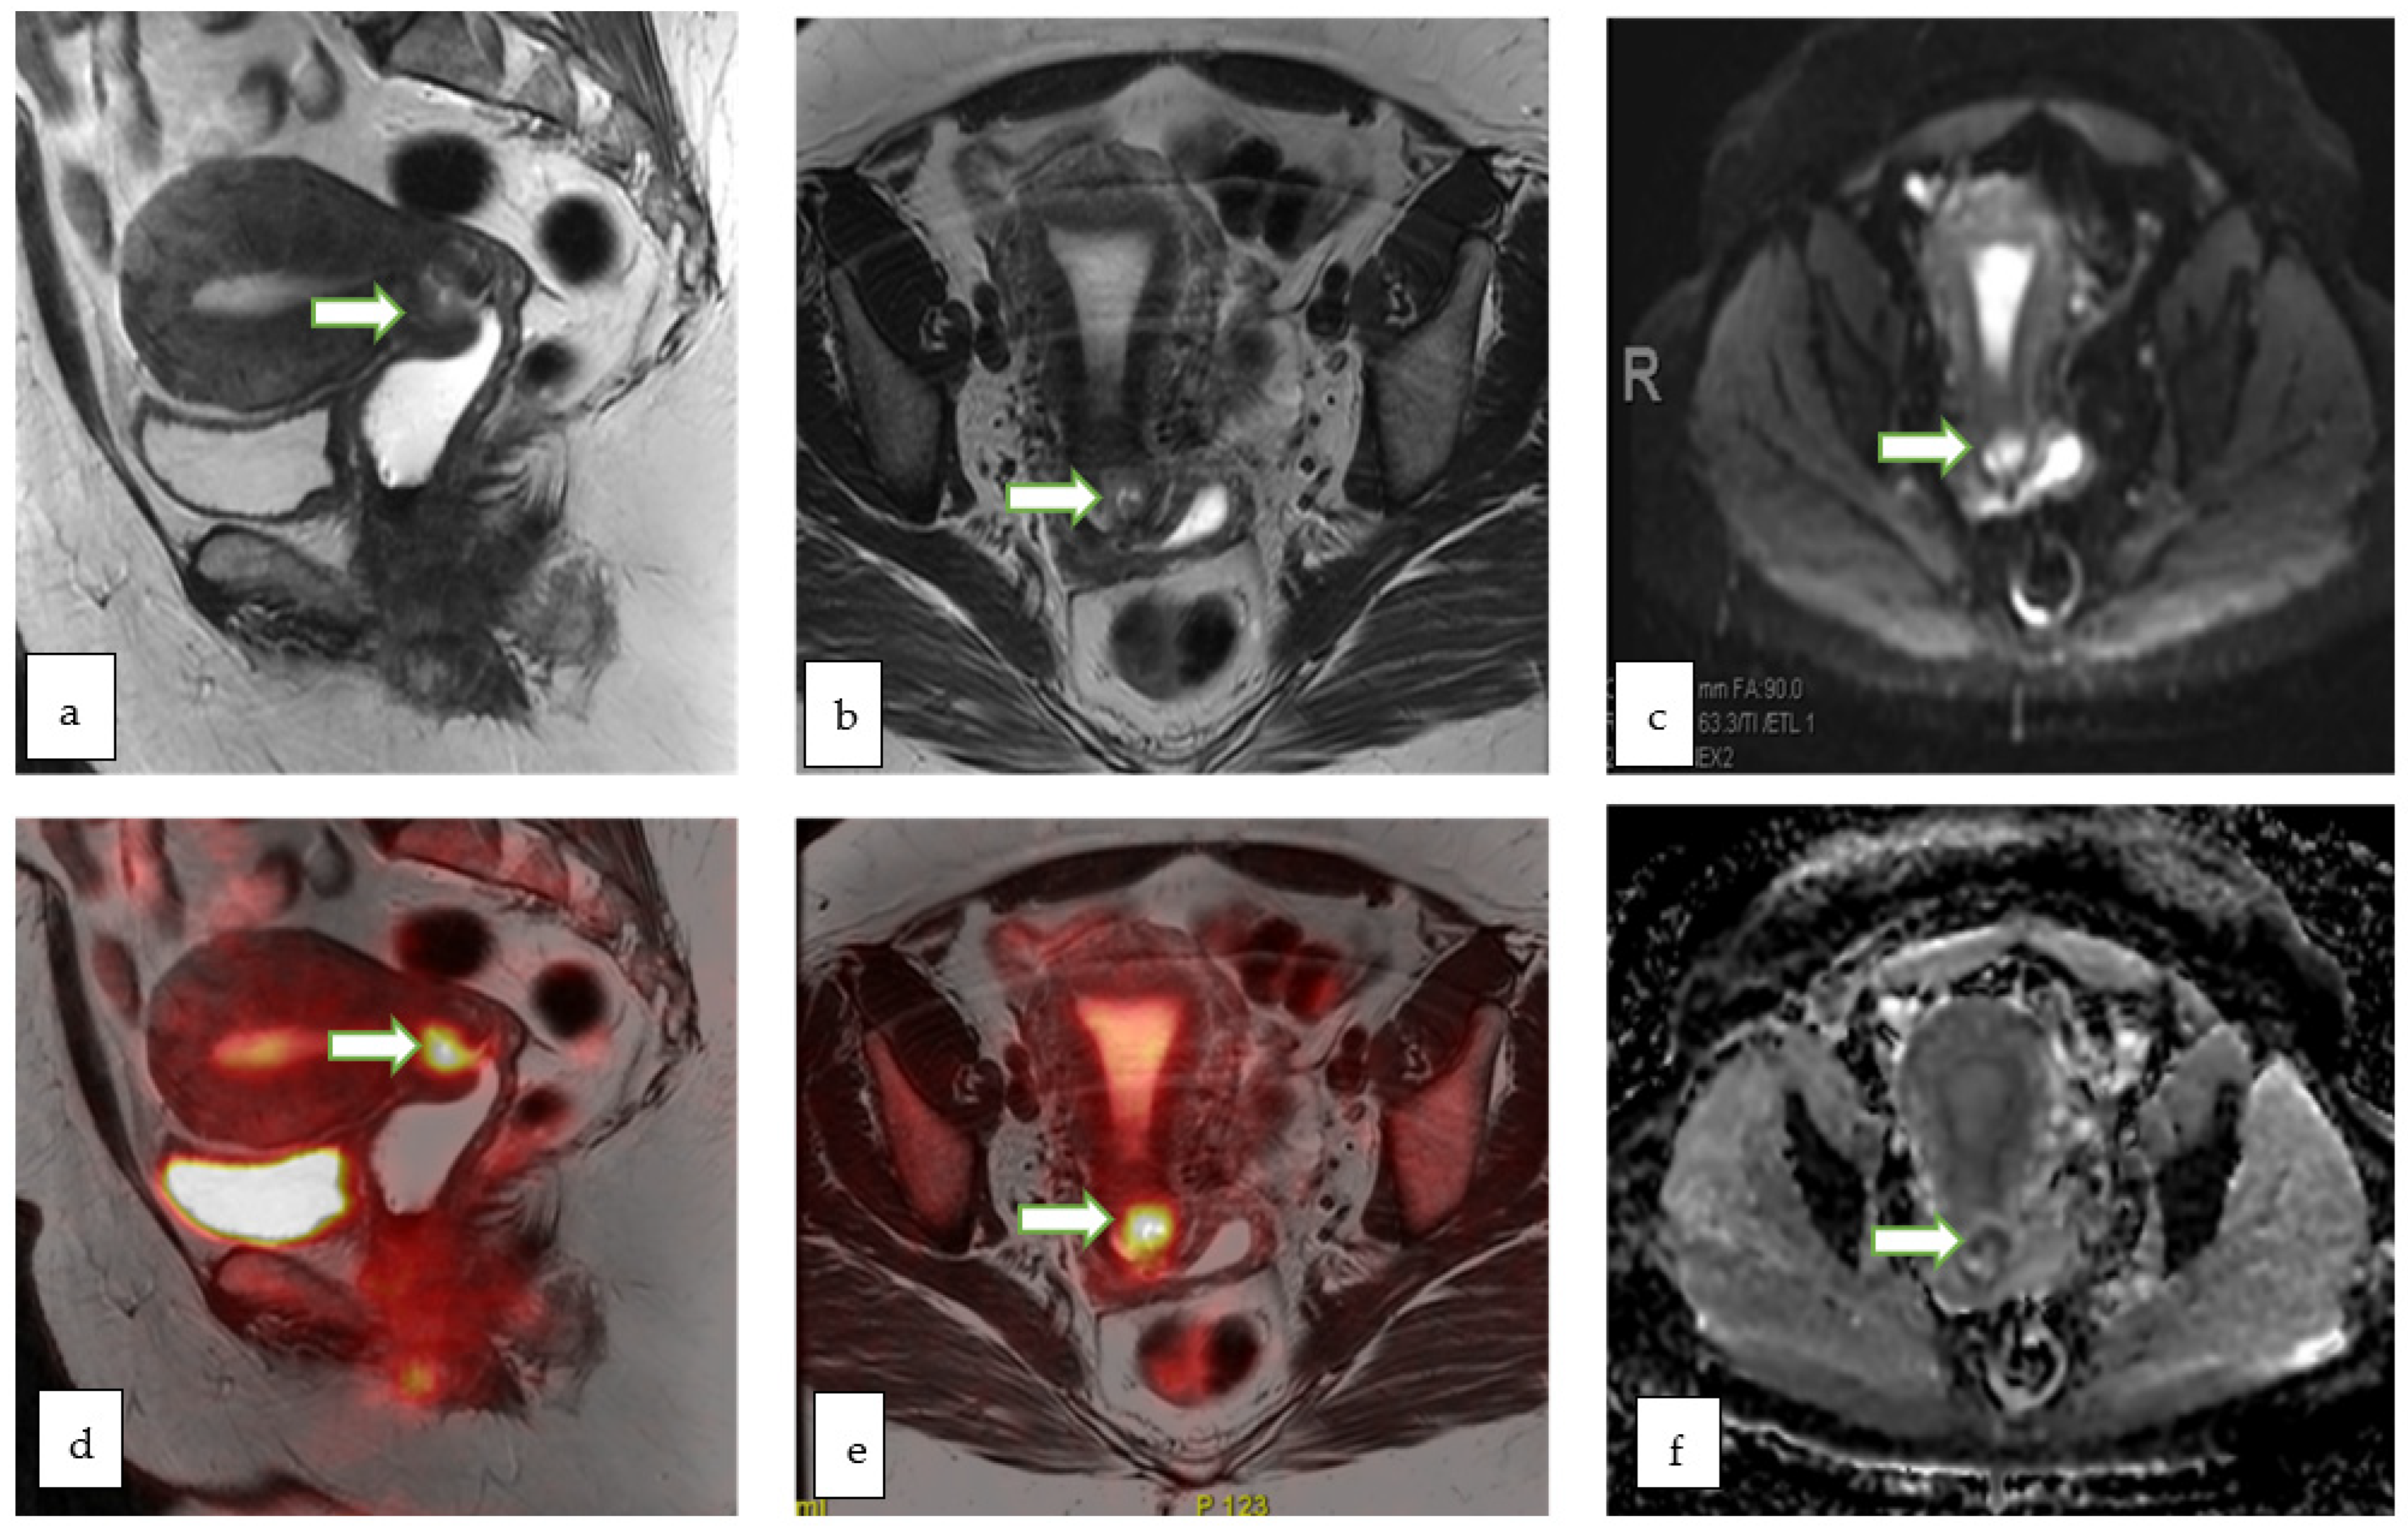

4.4. Molecular Imaging

4.5. Positron Emission Tomography-Computed Tomography (PET-CT)

4.6. PET-MRI

- Ohliger, M.A.; Hope, T.A.; Chapman, J.S.; Chen, L.M.; Behr, S.C.; Poder, L. PET/MR Imaging in Gynecologic Oncology. Magn. Reson. Imaging Clin. N. Am. 2017, 25, 667–684. [Google Scholar] [CrossRef]